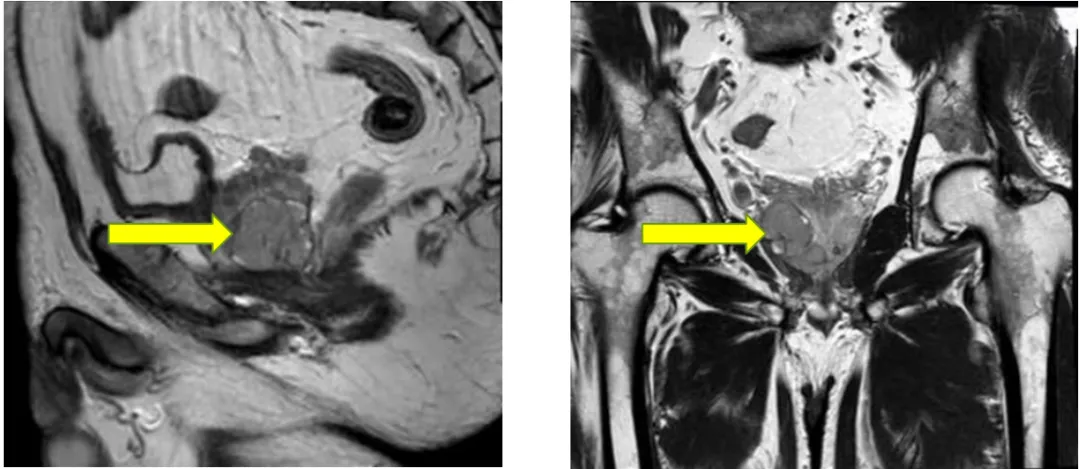

2025年9月12日 前列腺平扫+弥散(DWI)

(2024-11-28 vs 2025-9-12)

前列腺大小约为3.4cmx3.3cmx3.0cm,形态异常,右侧包膜欠光整,右侧周围带见结节状异常信号灶,T2WI低信号,T1WI低信号,DWI信号不高,边界欠清,长径约为0.9cm,左侧周围带信号不均匀减低,中央带及移行带信号不均。双侧精囊腺对称,充盈尚可。膀胱充盈可,其内未见异常信号灶。直肠因围脂肪间隙未见异常。扫描野内未见明显肿大淋巴结,扫描野内右侧股骨头及髋臼内见斑片状异常信号灶。

1. 结合病史,考虑前列腺右侧周围带肿瘤治疗后改变。

2. 右侧股骨头及髋臼异常信号灶,考虑退行性变可能。

前述改变与前片(2025-06)比较未见明显变化,建议隔期复查。